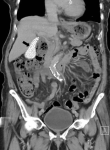

A 91-year-old woman presented with right flank pain for two days without fever, dysuria, trauma, or recent falls. Physical examination revealed no costovertebral angle tenderness. Laboratory tests showed an elevated C-reactive protein level of 3.6 mg/dL without leukocytosis. Urinalysis demonstrated pyuria and bacteriuria. She was treated empirically for acute pyelonephritis with intravenous cefoxitin, and urine culture later grew Escherichia coli sensitive to cephalosporins. Abdominal computed tomography (CT) revealed rupture of a right renal cyst. Incidentally, the gallbladder was filled with multiple small, round, hyperdense calculi, producing a striking "bag of stones" appearance (image 1, arrow). These findings were consistent with asymptomatic cholelithiasis. The patient's flank pain improved after a 7-day course of antibiotics. She was discharged in stable condition, and outpatient follow-up was unremarkable. Asymptomatic gallstones are commonly detected incidentally, and most patients remain symptom-free; therefore, expectant management is generally recommended. Prophylactic cholecystectomy is reserved for selected high-risk patients, such as those with porcelain gallbladder, large gallstones (>3 cm), anomalous pancreaticobiliary ductal junctions, gallbladder adenomas, or underlying hemolytic disorders.

Figure 1: abdominal CT showing numerous small, round hyperdense gallstones filling the gallbladder, giving a characteristic “bag of stones” appearance (arrow)